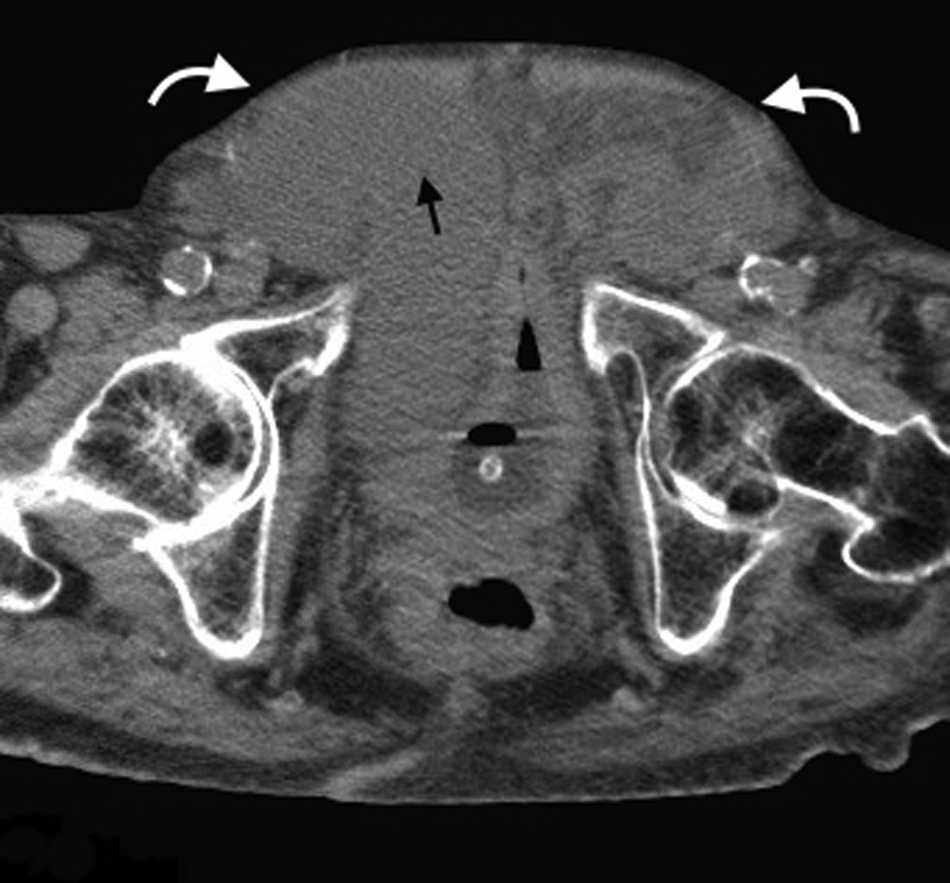

La hernia inguinal indirecta atraviesa el anillo inguinal interno, recorre el conducto y emerge a trav??s del anillo externo, sobresaliendo superior y externamente a los vasos epig??stricos inferiores. Puede extenderse por el conducto esperm??tico o el ligamento redondo hacia el escroto o los labios mayores, respectivamente. Es posible ver el cuello del saco herniario en el anillo inguinal profundo1 (fig. 1). Un hallazgo que ayuda a su caracterizaci??n es el signo del gancho. Este debe su nombre a la forma c??ncava que adopta la arteria epig??strica inferior en el plano axial en su curso proximal, al ser comprimida por una hernia indirecta6.

En lo que respecta a la directa, esta se ubica por encima del ligamento inguinal y medial a los vasos epig??stricos inferiores, y en general es adquirida. Su incidencia aumenta con la edad por el debilitamiento de la fascia transversal en el tri??ngulo Hesselbach1. Suele ser m??s frecuente en hombres y est?? menos asociada a la estrangulaci??n de las asas, posiblemente porque en general no atraviesa todo el curso del canal4 (fig. 2). El contenido del canal inguinal es comprimido lateralmente, mientras que su grasa se ubica como una luna creciente, produciendo el signo de la semiluna creciente (un hallazgo que ayuda a la caracterizaci??n de estas hernias)7.

El contenido est?? relacionado con los diferentes sitios de debilidad de la pared. A nivel epig??strico se encuentra una herniaci??n del antro g??strico, del l??bulo hep??tico izquierdo (fig. 14) o de la ves??cula biliar (fig. 15). Por su parte, dentro de las umbilicales puede haber grasa peritoneal, asas intestinales, implantes metast??sicos (n??dulo de la hermana Mar??a Jos??) (fig. 16) o l??quido asc??tico (fig. 17). En la hernia de Spiegel suele visualizarse grasa y asas intestinales, mientras que las obturatrices muchas veces son descubiertas porque el paciente presenta un cuadro de obstrucci??n intestinal mec??nica que ayuda al diagn??stico. En cuanto a la lumbar, se puede herniar grasa, el polo renal o el l??bulo hep??tico derecho (fig. 18). En el caso de la inguinal, esta tiene un contenido muy variado, aunque la grasa peritoneal y las asas son los m??s frecuentes (fig. 19). Adem??s, puede herniar ??rganos intrapelvianos, como la vejiga (cistocele) (fig. 20) o el ap??ndice (hernia de Amyand)20 (fig. 21), y si se produce la herniaci??n del ap??ndice dentro del canal crural, se denomina hernia De Garengeot9 (fig. 22). Finalmente, en las eventraciones se observan asas de intestino delgado y grueso, ri??ones trasplantados (fig. 23) y vejigas (fig. 24).